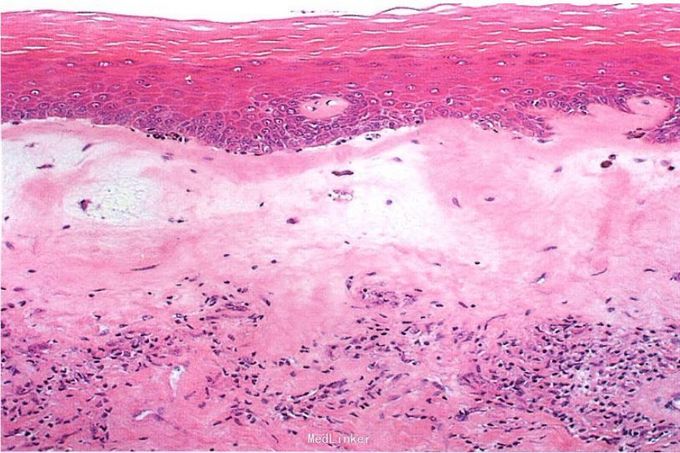

皮肤科检查:双侧大阴唇轻度水肿,略充血,表面轻度苔藓样变,外阴部分皮肤略有萎缩,颜色发白,较周围皮肤发亮。病理活检提示:表皮角化过度,基底细胞灶状液化变性,真皮上部胶原纤维均质化,真皮中部可见以淋巴细胞为主的炎性细胞带状浸润。

诊断:硬化性萎缩性苔藓。给予复方曲安缩松霜外用,每天2次,1周后瘙痒消失,1个月后外阴皮肤基本恢复正常。复方曲安缩松霜外用改为每天1次,维持治疗1个月后停用。